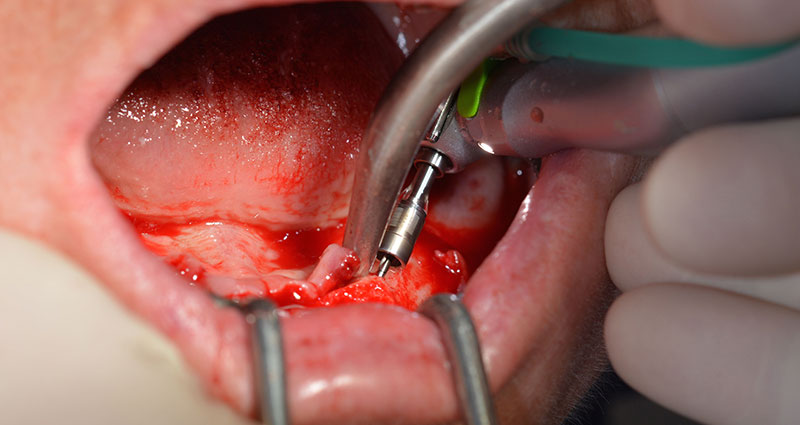

Il protocollo chirurgico per il sistema di implantologia utilizzato (SKY, Bredent medical) prevede una velocità di 1.200 giri/min per la perforazione pilota (Fig. 7 - 9).

Questa è la prossima posizione programmata nel sistema Implantmed. Qui è possibile vedere il contrangolo W&H impugnato a un angolo di 45 gradi in posizione medio-caudale, nella zona del 45, al fine di salvaguardare il nervo mentoniero. Il forame mentoniero è un punto di riferimento anatomico per tutte le perforazioni in quest'area. I fori successivi sono realizzati con una velocità ridotta, pari a 300 giri/min (Fig. 10 e 11).